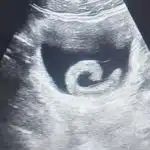

ซึ่งจากถ่ายภาพทางรังสีวิทยาพบว่า “กระดูกหักตามร่างกายไม่หัก แต่ปอดอักเสบรุนแรงทั้ง 2 ข้าง” ซึ่งน่าจะเป็นสาเหตุหลักของอาการป่วยนี้

เครดิตภาพ : น.ส.ณัฐรุรี คำชมภู นักวิทยาศาสตร์ ชำนาญการ โรงพยาบาลสัตว์ คณะสัตวแพทยศาสตร์ มหาวิทยาลัยเกษตรศาสตร์ วิทยาเขตบางเขน กรุงเทพฯ